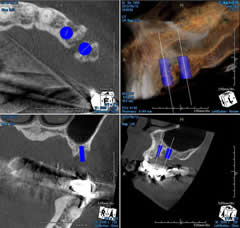

当院の歯科用CTはあらかじめシュミレーションできる専用ソフトが内蔵されていますので、上顎では鼻腔底や上顎洞までの距離、下顎では下顎管やオトガイ孔までの距離が正確に測定でき、術前にどのサイズのインプラントを選択するのがベストかをしっかり把握することができます。

さらに術中でのCT撮影により極めて安心安全な手術をおこなうことが可能となります。